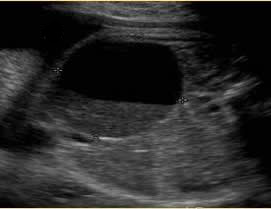

Above. Ovarian cyst. Case 2. Third trimester ultrasound. Ovarian cyst is right sided with echos suggestive of sediment or blood. The cyst exceeds the 40 mm to 50 mm cutoff in size suggesting an increased risk for adverse outcome.